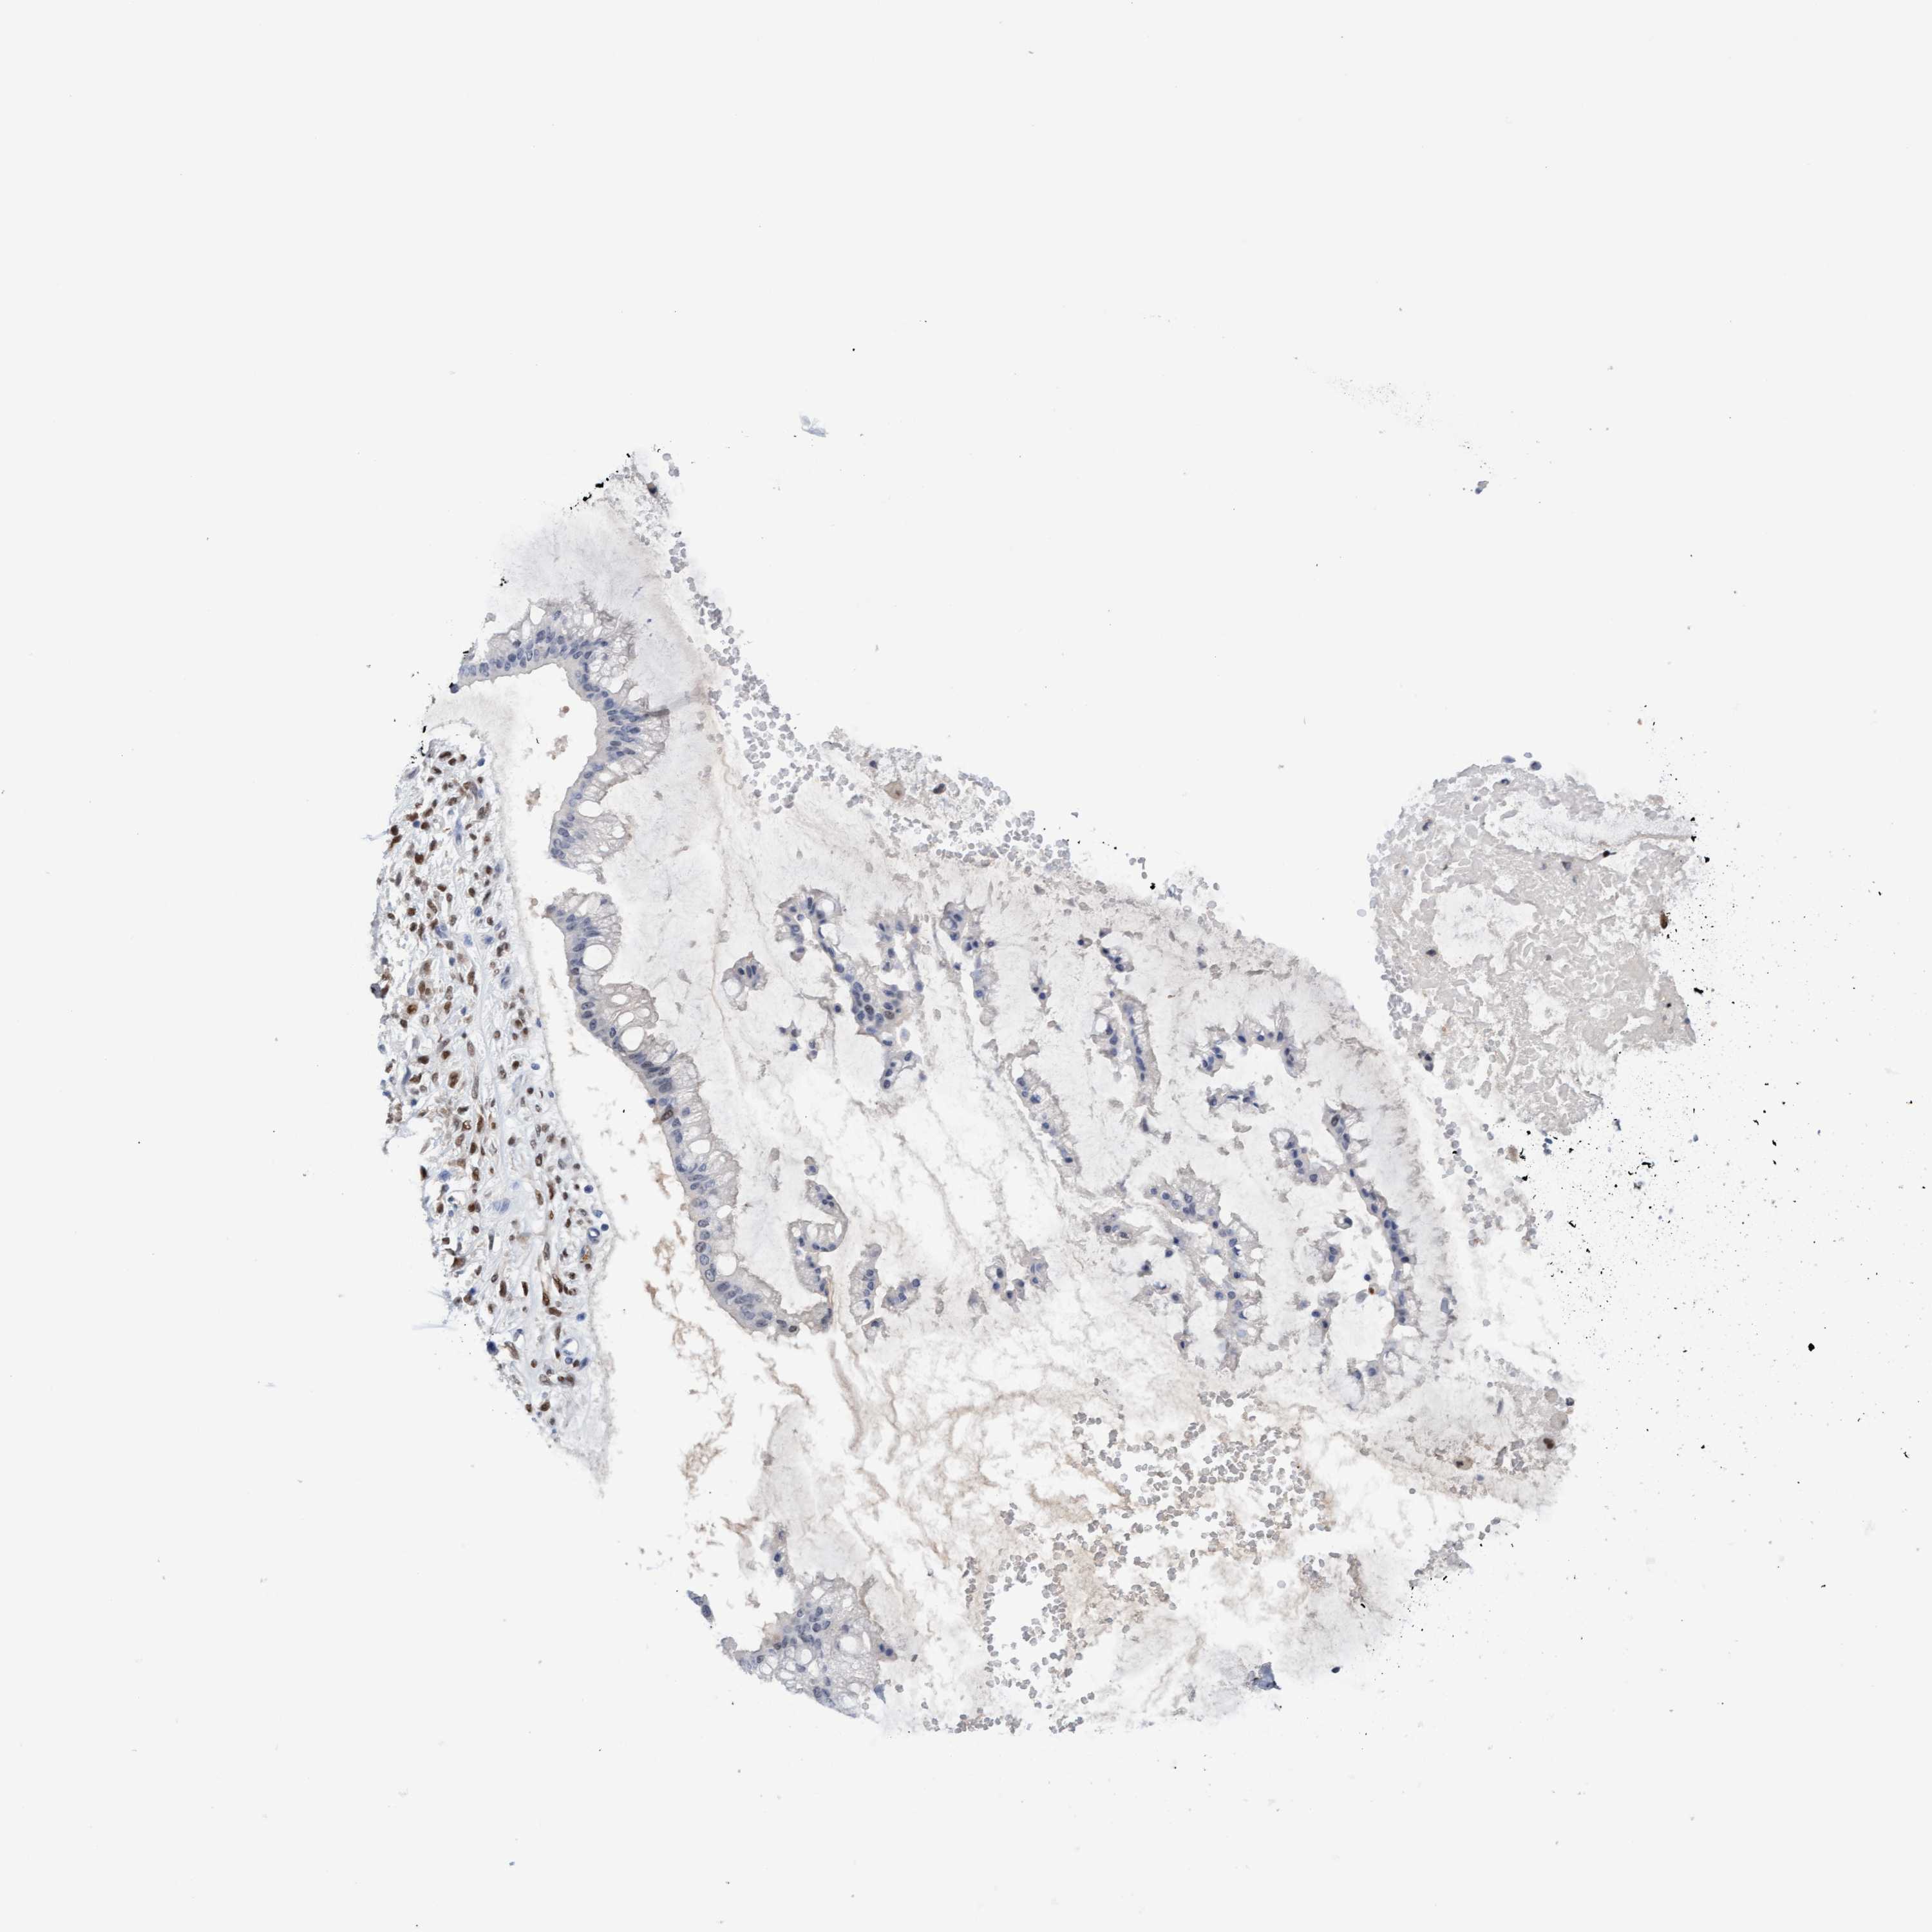

OVARIAN CANCER - Protein expressioni

A mouse-over function shows sample information and annotation data. Click on an image to view it in a full screen mode. Samples can be filtered based on level of antibody staining by selecting one or several of the following categories: high, medium, low and not detected. The assay and annotation is described here.

Note that samples used for immunohistochemistry by the Human Protein Atlas do not correspond to samples in the TCGA dataset.

Antibody stainingi

Antibody staining in the annotated cell types in the current human tissue is reported as not detected, low, medium, or high, based on conventional immunohistochemistry profiling in selected tissues. This score is based on the combination of the staining intensity and fraction of stained cells.

Each image is clickable and will lead to virtual microscopy that enables deeper exploration of all samples and also displays staining intensity scores, fraction scores and subcellular localization as well as patient and tissue information for each sample.

Antibody HPA023139

Staining

High

Medium

Low

Not detected

Intensity

Strong

Moderate

Weak

Negative

Quantity

>75%

75%-25%

<25%

None

Location

Nuclear

Cytoplasmic/membranous

Cytoplasmic/membranous,nuclear

Cystadenocarcinoma, serous, NOS

Carcinoma, endometroid

Cystadenocarcinoma, mucinous, NOS

Carcinoma, NOS